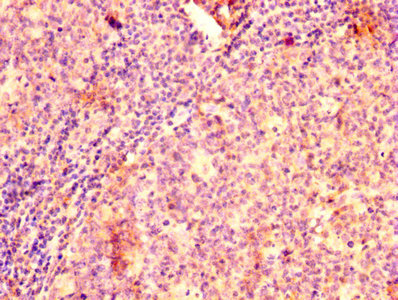

IHC image of CSB-PA00969A0Rb diluted at 1:500 and staining in paraffin-embedded human spleen tissue performed on a Leica BondTM system. After dewaxing and hydration, antigen retrieval was mediated by high pressure in a citrate buffer (pH 6.0). Section was blocked with 10% normal goat serum 30min at RT. Then primary antibody (1% BSA) was incubated at 4°C overnight. The primary is detected by a biotinylated secondary antibody and visualized using an HRP conjugated SP system.